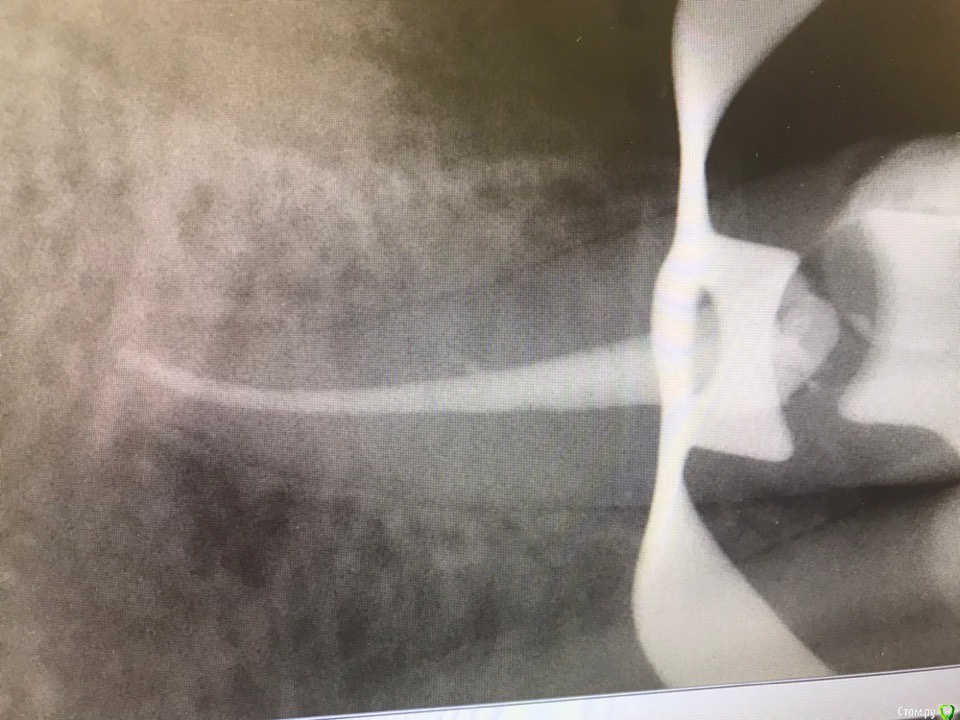

1586Doc Опубликовано 30 марта, 2019 Автор Поделиться Опубликовано 30 марта, 2019 (изменено) Еще немного работы45 зуб эндо и пломба и 46 зуб эндо и пломба на снимке справа Изменено 30 марта, 2019 пользователем 1586Doc Ссылка на комментарий